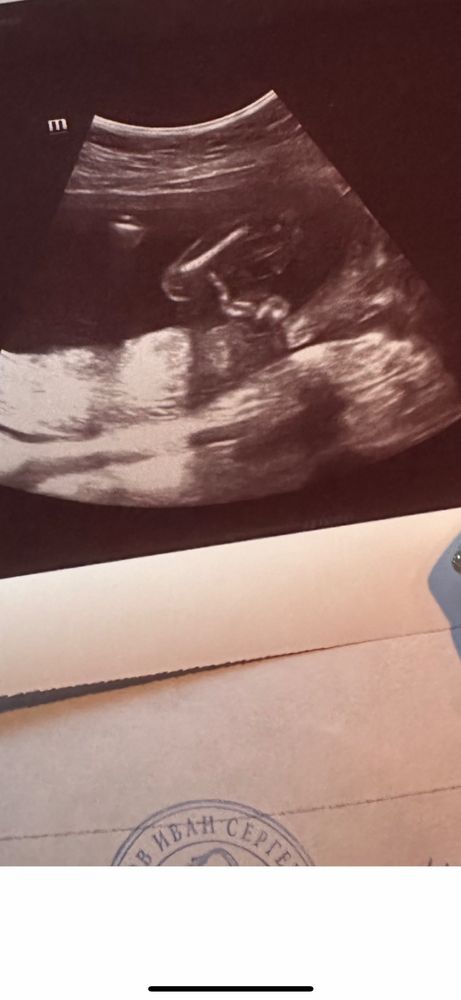

Пол малыша на 18 акушерской неделе

у меня вопрос возник, ошибались ли у кого-то на 2 скрининге с полом? Вчера на платном скрининге сказали мальчик. Я не поверила, сегодня сходила в другую клинику- опять же, платно . Там врач первые несколько минут уверенно «да тут девочка 100%», а по итогу завершил все мальчиком 🤦🏻♀️ очень хочу девчонку, понятно, что и мальчика буду любить не меньше. Но надеяться продолжаю. Срок по месячным 18 и 2.